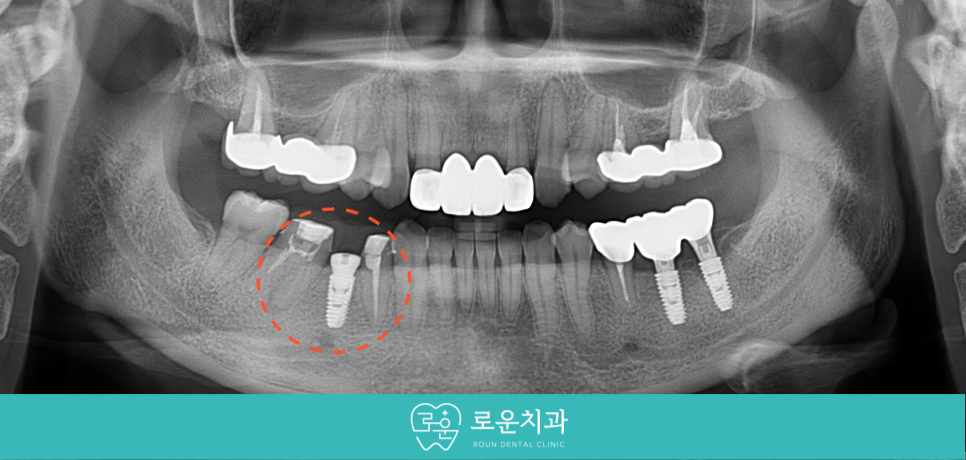

식립 후 임플란트가

주변 잇몸뼈와 단단히 결합되었을 때

양옆의 크라운 보철물과 같은

지르코니아로 최종 보철물 제작을 도와드리면서

치료를 마무리해 드렸습니다.

[치료 전 -> 후]

치료 기간 :

1차 2023/12/2 ~ 2024/4/23

2차 2023/5/13 ~ 2024/8/9

환자분께서는 그동안 어금니의 통증으로 인해

불편감이 많으셨지만

치료를 통해 통증이 사라지고

편안해지셔서 만족해하셨습니다.